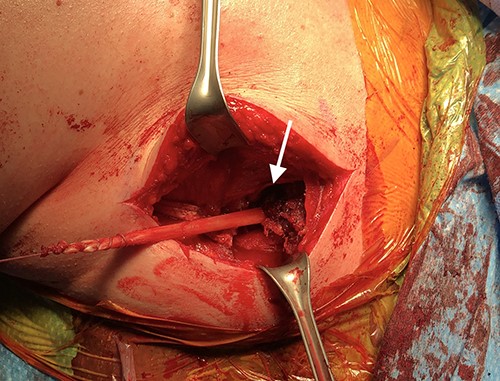

An incision was made using a deltopectoral approach distally. The sternal border of the pectoralis major muscle was identified, traced out laterally, and removed sharply from the periosteum (Fig. 3). After mobilizing the pectoralis major, a tibialis anterior autograft was prepared on the back table; each side was tagged with a fiber loop, and a Pulvertaft weave was used to connect the graft to the pectoralis major (Figs 4 and 5).

Intraoperative photograph showing the surgical exposure using the deltopectoral approach (A). The pectoralis major muscle is identified and tagged, demonstrated by the white arrow (B).